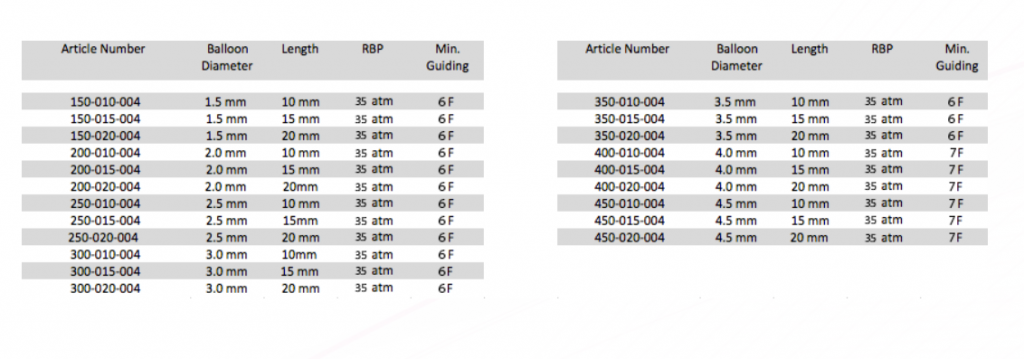

Tekniset tiedot:

– Min Ohjauskatetri 6 F

– Kaksi platinamerkkiä kaikkiin kokoihin: saatavana halkaisijaltaan 1,5 – 4,5 mm